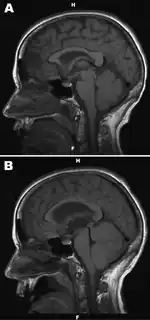

| a,b) Noncontrast, sagittal T1-weighted magnetic resonance image of brain with suspected Powassan virus encephalitis | |